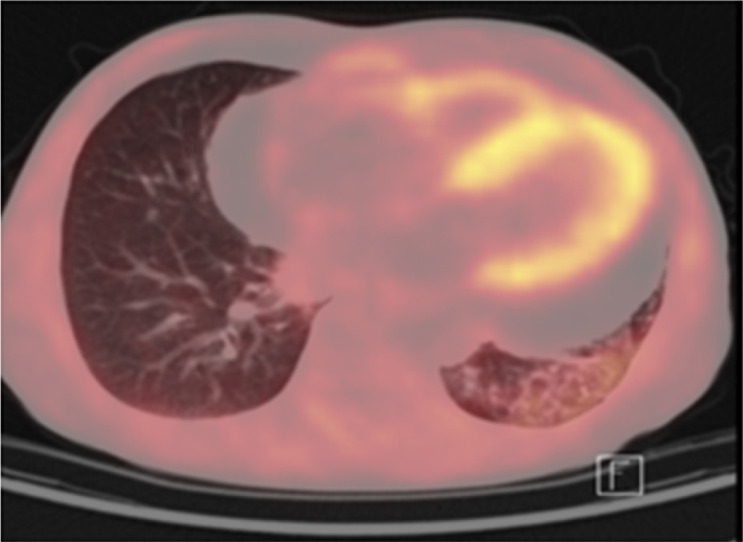

Abstract Image